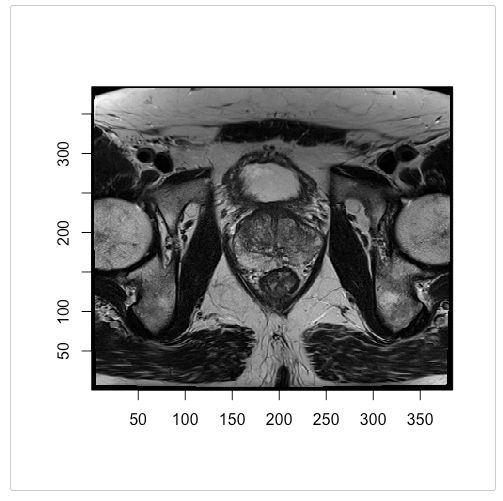

2. radtools: 提供一组用于以DICOM和NIfTI格式操作医学图像数据的实用程序,允许将图像元数据简单地转换为熟悉的R数据结构,例如列表、数据帧.